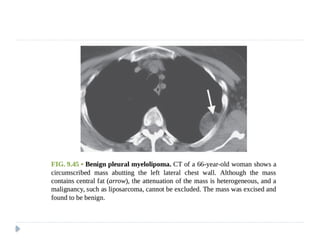

Benign pleural fibroma.

Enhanced CT reveals a soft tissue

intrafissural mass with coarse

calcifications, pathologically consistent

with a benign pleural fibroma.